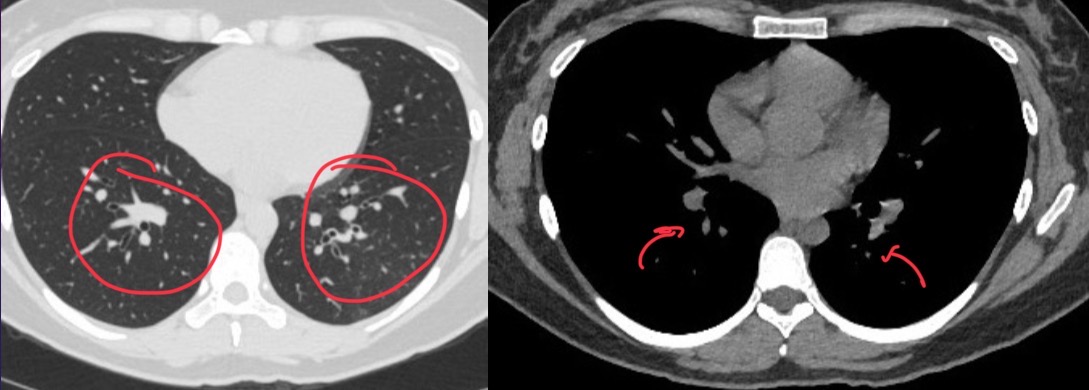

What does chest scan show

Left pneumothorax, atelectasis in right upper and left lower lobes